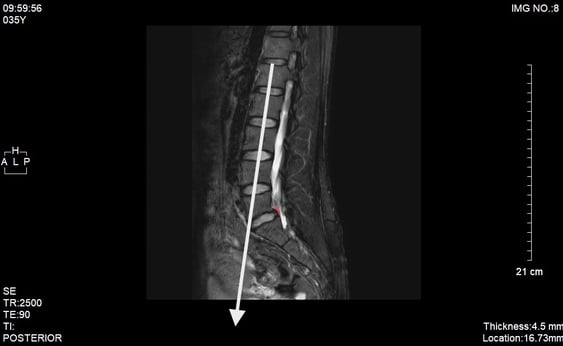

腰椎を通る重心が後方にあり、腰仙関節に負荷がかかり過ぎていた。

白いラインが概ね垂直で、第3腰椎椎体の中心から垂直ライン上に仙骨の岬角があり、さらに第3腰椎から上の腰椎椎間関節は胸椎に向けて緩やかに伸展しているのが理想